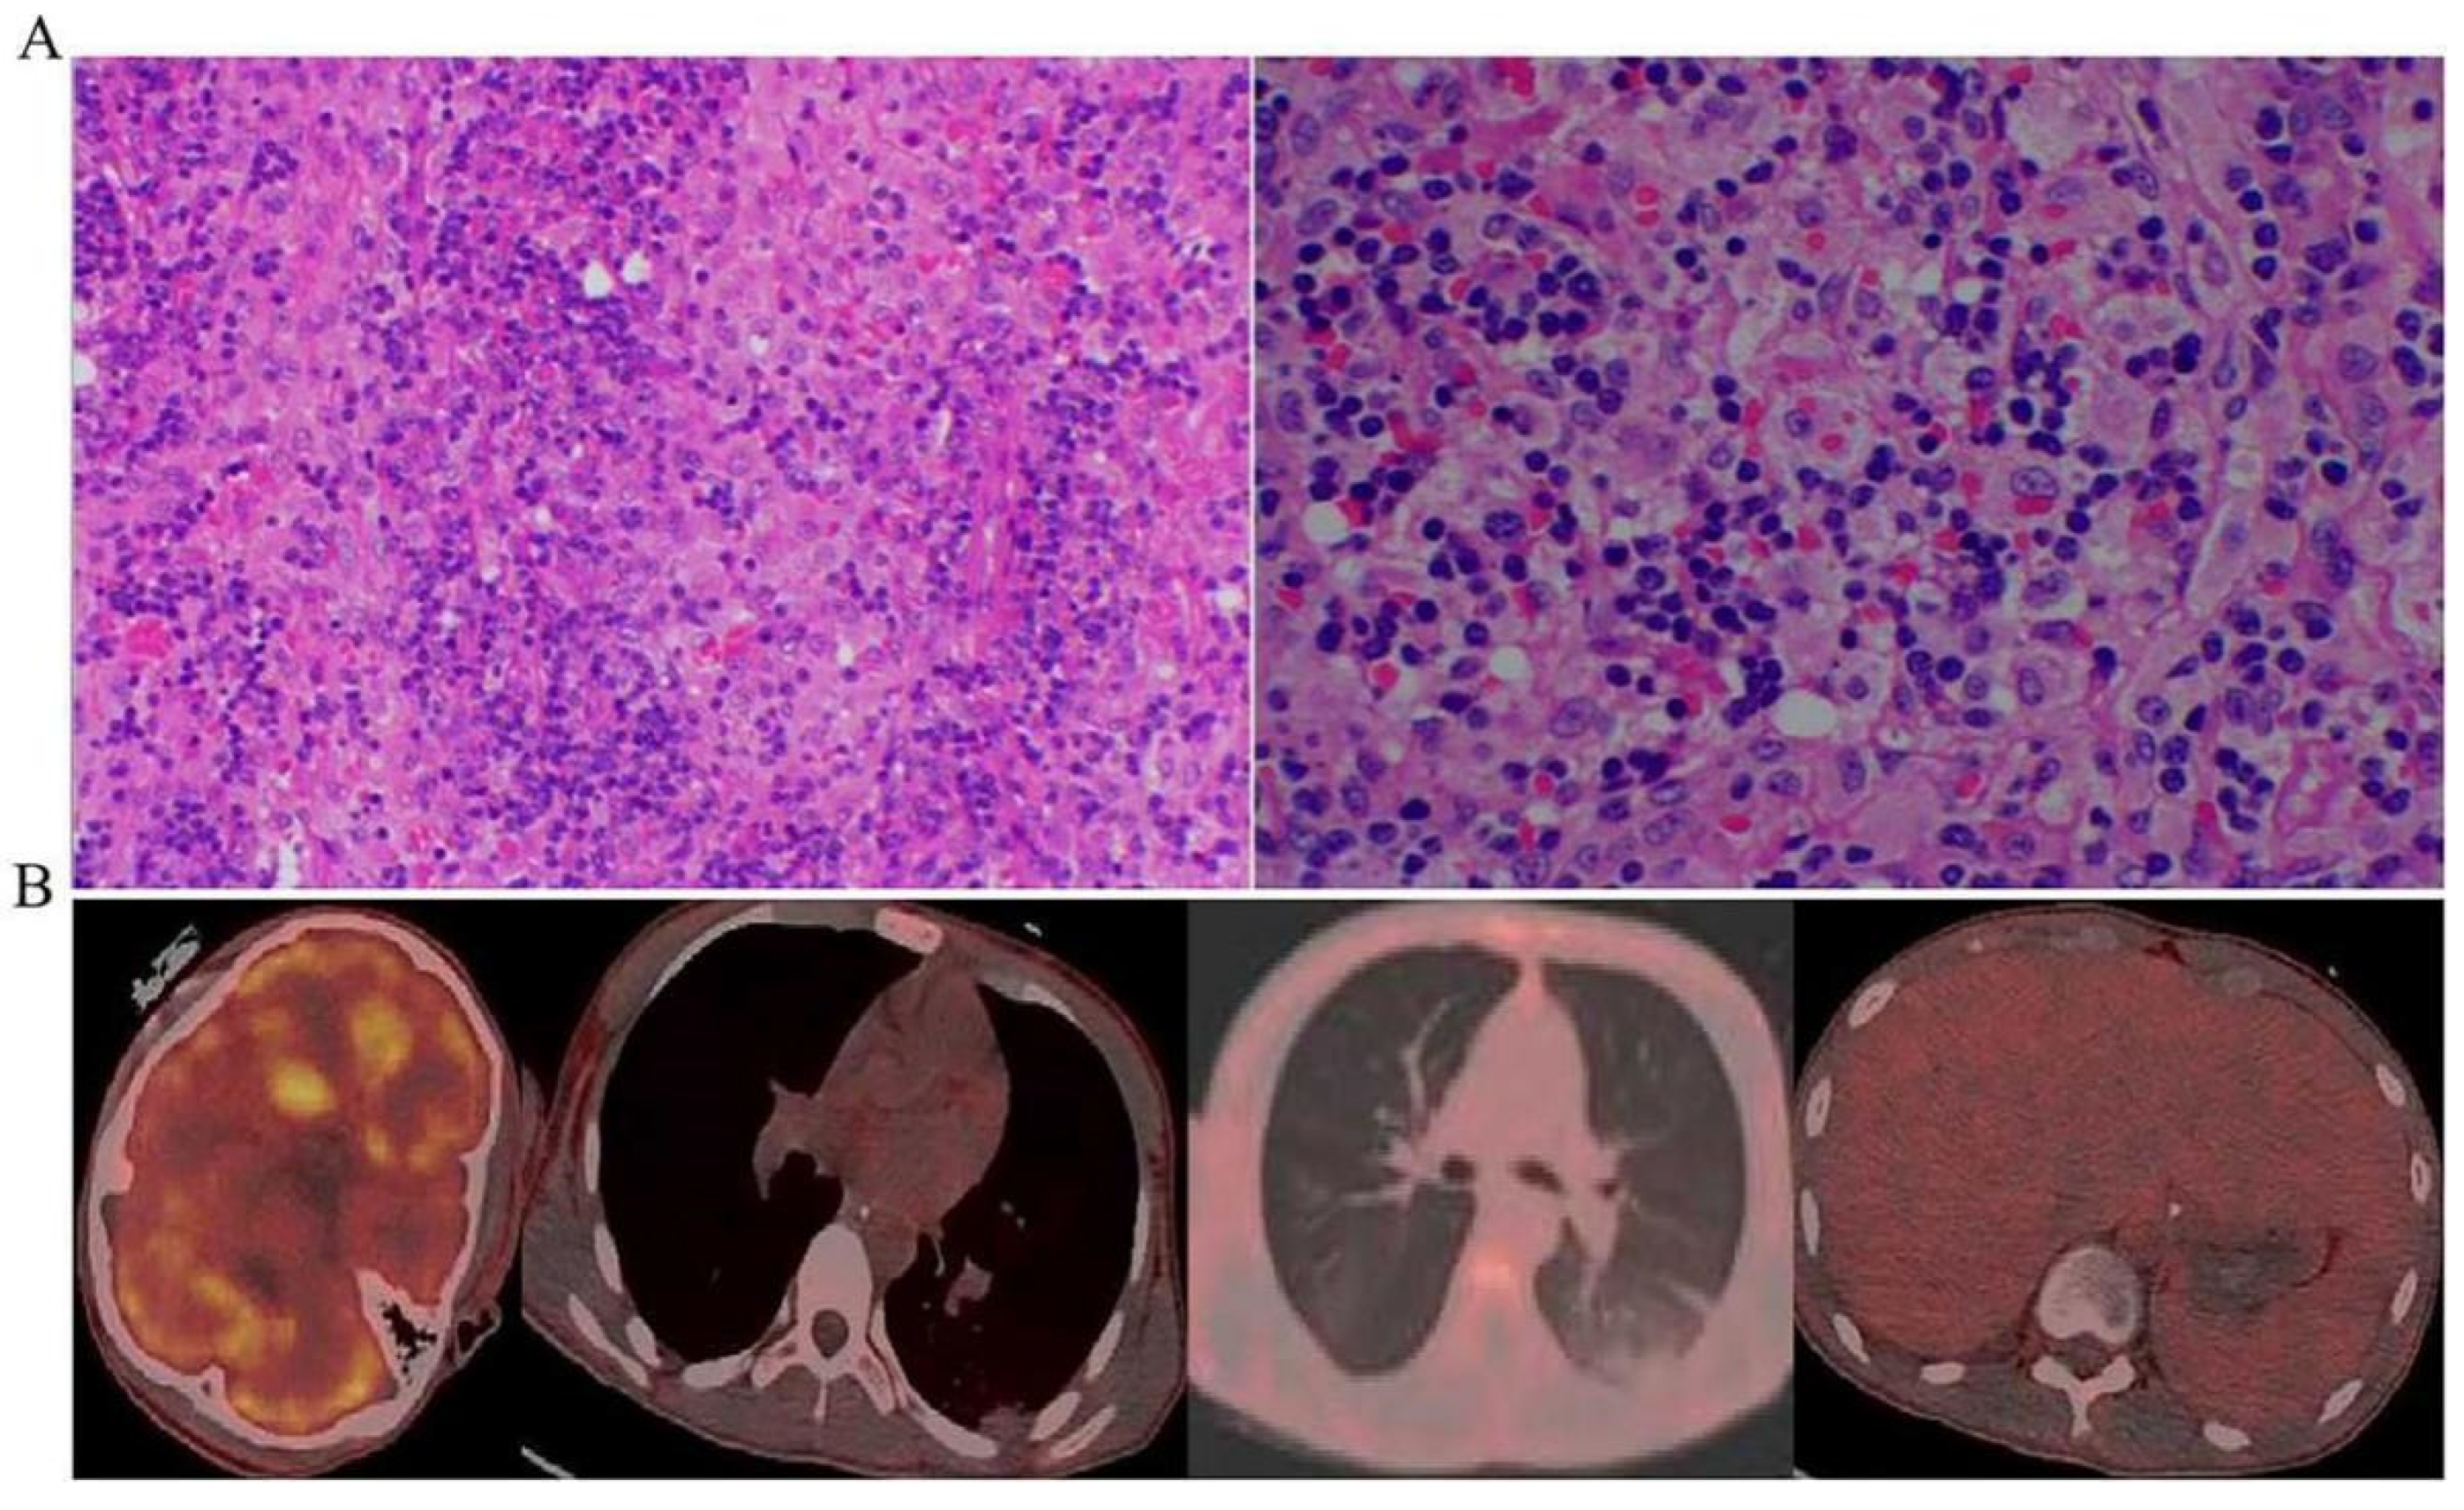

- The chest computed tomography (CT) scan showed inflammatory exudate and oedema in both lungs, bilateral pleural effusion, enlarged liver and spleen, and brain cell oedema (Figure 1).